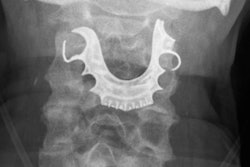

She went to the hospital immediately and a radiograph revealed that her two fake teeth attached to a plate were stuck halfway down her throat. Clinicians advised her that trying to retrieve the dentures would be more dangerous than waiting 72 hours for the fake teeth to pass through her digestive system.